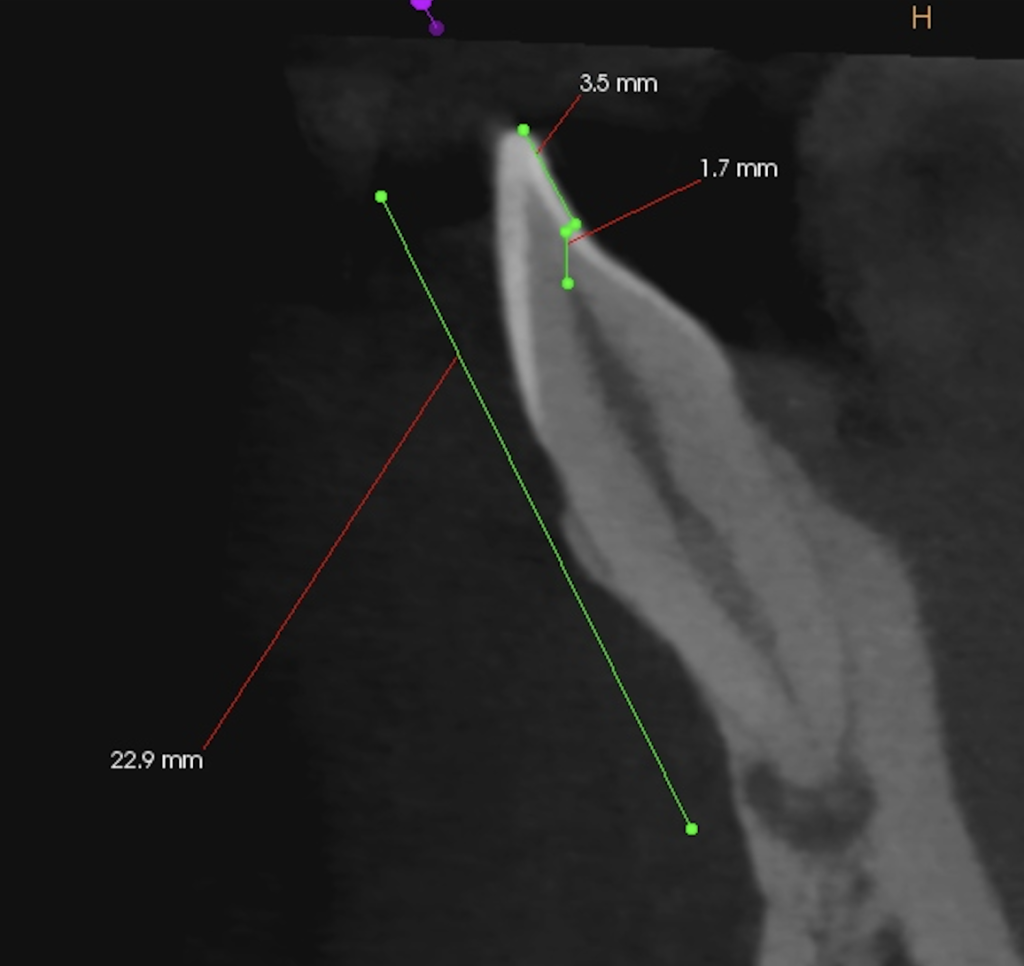

切端から3.5mmの部分を1.7mm削合すると露髄し、根管治療を行うための根管に到達できるだろう。

ここがこの治療の唯一の肝と言える。